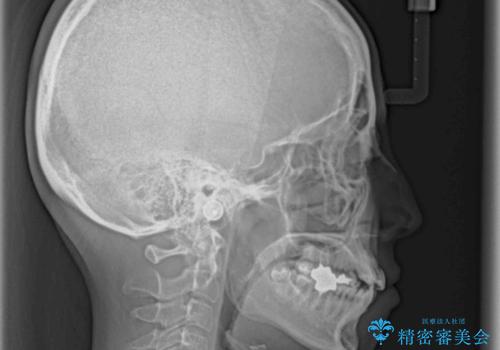

- 八重歯と、それによる口元の膨らみを気にして来院された患者様です。

八重歯・デコボコの解消とともに、前方に張り出した上顎前歯を引っ込めることを目的とし、上下左右の第一小臼歯4歯を抜歯をしてワイヤー矯正により治療することとしました。